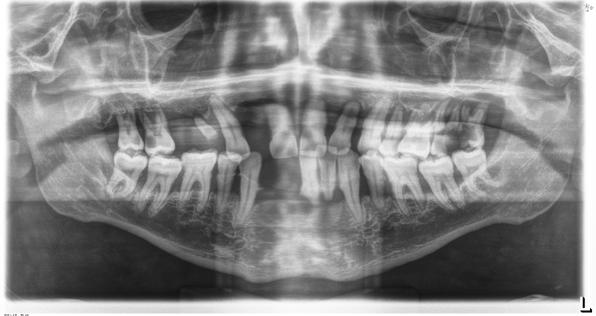

En la radiografía panorámica se observaron 28 dientes permanentes erupcionados y los gérmenes de los terceros molares, la longitud radicular es de 2:1; los senos, cóndilos y ramas mandibulares son simétricas, no presenta patologías (Figura 3).

Figura 3. Radiografía panorámica inicial.

Calidad y dirección